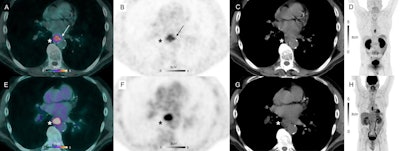

According to the findings, Ga-68 NODAGA-RGD-PET/CT detected positive radiotracer uptake in 10 primary sites (eight for primary tumors and two for local relapse suspicion), six lymph nodes, and three skeletal sites. F-18 FDG-PET/CT detected positive uptake in the same sites but also in 16 additional lymph nodes and one adrenal gland.

However, the researchers noted that while F-18 FDG uptake was homogenous inside all the confirmed primary sites (n = 9), Ga-68 NODAGA-RGD showed more heterogenous uptake in six out of the nine confirmed primary sites (67%). These sites were involved in potential early angiogenesis, with activity on imaging seen mostly in the periphery of the tumor and extending into surrounding tissue in five out of the nine confirmed primary sites (56%), they wrote.